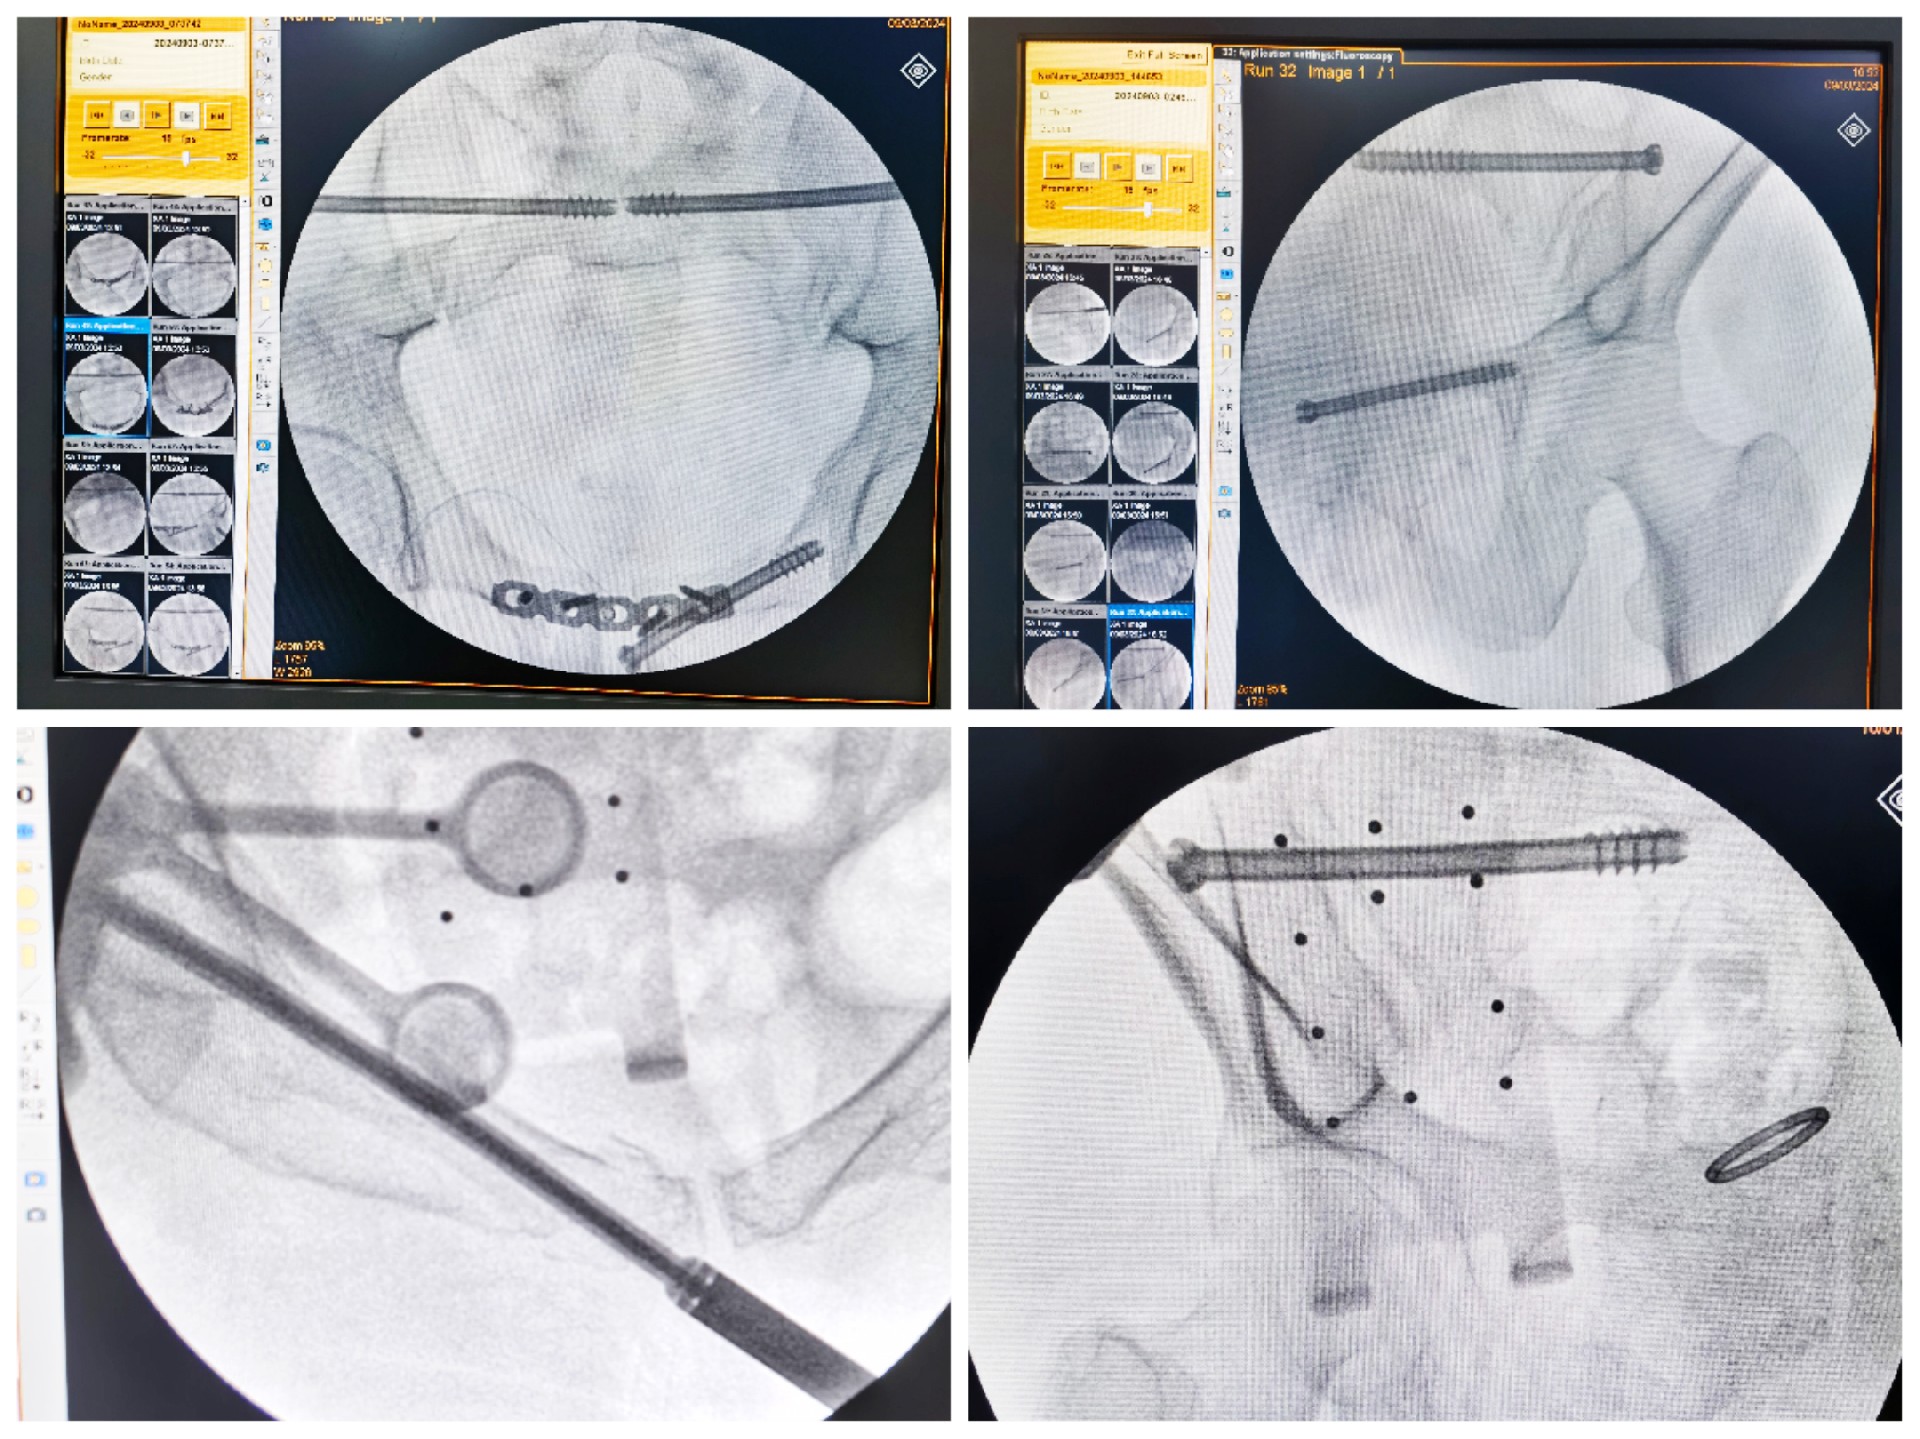

傳統(tǒng)的骨盆骨折微創(chuàng)手術(shù)中,骶髂螺釘?shù)嚷葆斨萌氲碾y點(diǎn)在于骨盆部位解剖十分復(fù)雜,螺釘置入如有偏差極易損傷重要神經(jīng)及血管,手術(shù)不僅依靠手術(shù)醫(yī)師豐富的經(jīng)驗(yàn),還需要術(shù)中反復(fù)的C型臂透視及調(diào)整,對(duì)患者及醫(yī)生都有較大輻射。而利用HoloSight知見創(chuàng)傷骨科機(jī)器人進(jìn)行骨盆骨折微創(chuàng)手術(shù),通過(guò)高精度光學(xué)定位追蹤技術(shù)與混合現(xiàn)實(shí)技術(shù),使整個(gè)微創(chuàng)手術(shù)全程可視化,可以在電腦屏幕上實(shí)時(shí)顯示螺釘?shù)木珳?zhǔn)置入位置,降低手術(shù)風(fēng)險(xiǎn),提高手術(shù)效率及安全性。

術(shù)前,手術(shù)團(tuán)隊(duì)認(rèn)真分析討論病例,全面掌握骨盆骨折微創(chuàng)治療的關(guān)鍵技術(shù),提前設(shè)計(jì)手術(shù)方案并反復(fù)模擬演練手術(shù)過(guò)程。術(shù)中,利用HoloSight知見創(chuàng)傷骨科機(jī)器人規(guī)劃骨折復(fù)位方案及定位螺釘通道,實(shí)現(xiàn)精準(zhǔn)微創(chuàng)手術(shù)。手術(shù)通過(guò)不足1cm小切口完成,最大程度地減少了術(shù)中出血,術(shù)中幾乎都是一次性成功精準(zhǔn)微創(chuàng)地置入內(nèi)固定螺釘,減少了醫(yī)源性操作對(duì)骨折周圍骨質(zhì)的影響,實(shí)現(xiàn)骨折微創(chuàng)固定的同時(shí)盡可能提高骨折固定的穩(wěn)定性,為術(shù)后患者的快速康復(fù)創(chuàng)造了有利條件。